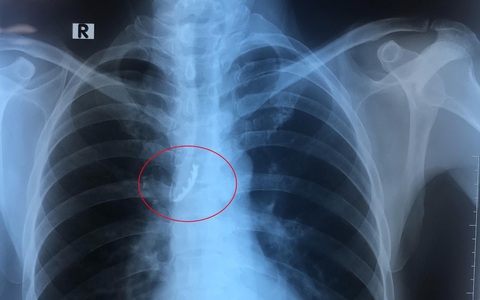

TTO - Ngày 24-5, các bác sĩ nội soi Bệnh viện Đa khoa trung ương Cần Thơ vừa thực hiện nội soi can thiệp lấy hàm răng giả 4 chiếc, bị kẹt trong phế quản một nam bệnh nhân.

TTO - Trong lúc ngủ, một cụ ông 95 tuổi (ở TP Đồng Hới, Quảng Bình) quên tháo hàm răng giả, khiến hàm răng rơi xuống cổ. Sáng dậy cụ kêu đau tức ngực và không nuốt được nên người nhà đưa vào cấp cứu.

TT - Vội vàng ăn khuya sau một ngày làm việc vất vả, ông D.B.S. (60 tuổi, ở Q.5, TP.HCM) đã nuốt luôn bốn chiếc răng giả.